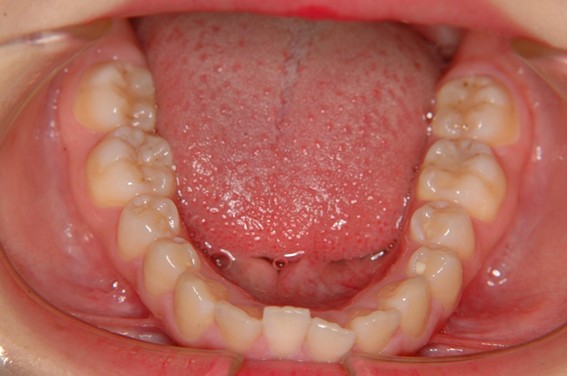

| 主訴 | 前歯が逆に噛んでいる。 |

| 治療内容 | 表側ワイヤー矯正、ジルコニア補綴を行いました。 |

| 治療費 | ワイヤー矯正660,000円(税込) ジルコニア176,000円(88,000円×2歯)(税込) |

| 治療期間 | 30ヶ月 |

| 治療回数 | 30回 |

| 想定されたリスク | 歯根吸収、歯髄壊死、歯髄充血、歯肉退縮のリスクがありました。 |

骨格性Ⅲ級・前歯部反対咬合の症例でした。反対咬合のまま治療していた前歯のサイズ不調和を、表側ワイヤー矯正とプロビジョナルクラウンで調整。正中を整え、犬歯・臼歯ともⅠ級、適切なオーバージェット(上下前歯の前後的な距離)・オーバーバイト(上下前歯の垂直的な重なり)に仕上げました。